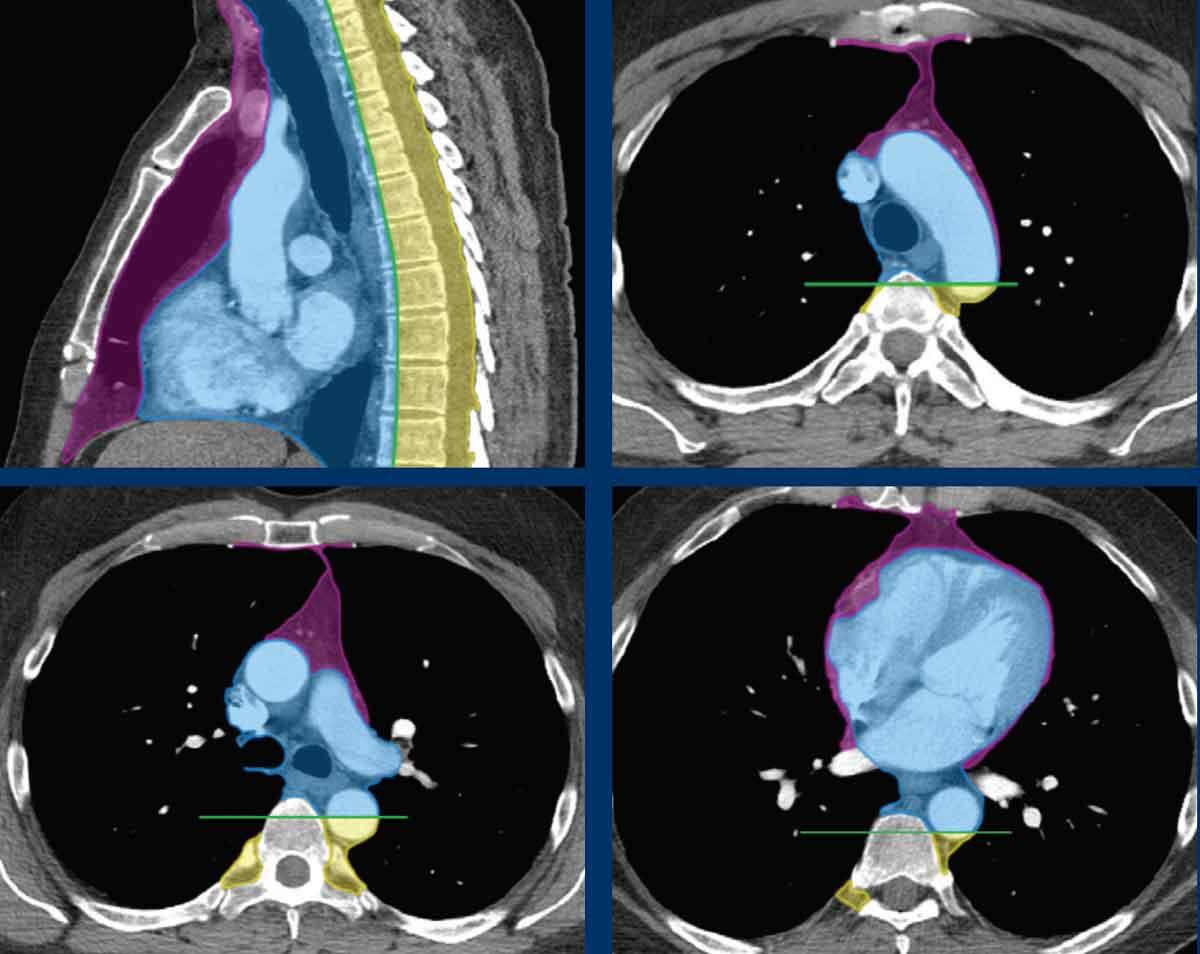

Phân loại các khoang trung thất theo ITMIG

Hầu hết các phân loại hình ảnh học trong quá khứ đều dựa trên các mốc giải phẫu tùy ý được xác định trên phim X-quang ngực thẳng bên, chia trung thất thành khoang trước, khoang giữa và khoang sau.

Một hệ thống phân loại mới dựa trên hình ảnh cắt lớp, chủ yếu là chụp cắt lớp vi tính đa dãy đầu thu (CT), đã được Nhóm Nghiên cứu Quốc tế về Bệnh lý Ác tính Tuyến Ức (ITMIG) xây dựng và hiện được chấp nhận là tiêu chuẩn mới.

Khoang trước mạch chứa tuyến ức, mô mỡ, hạch bạch huyết và tĩnh mạch tay đầu trái.

Lưu ý rằng ranh giới phía sau là mặt trước của màng ngoài tim khi nó bao quanh tim theo hình cong.